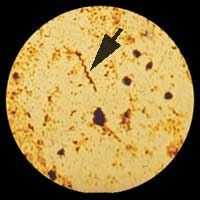

3 - 3 Examen après coloration spéciale (Ziehl-Neelsen) : Les bacilles acido-alcoolo-résistants (BAAR) compte tenu de la composition de leur paroi sont détectés spécifiquement. Il s'agit du groupe des mycobactéries dont le bacille tuberculeux (Bacille de KOCH/BK) colorées en rouge sur un fonds bleu. Ce contraste de coloration permet une recherche plus facile sur un frottis. D'ailleurs, l'usage actuel d'un colorant fluorescent (auramine) confirme l'intérêt d'une visualisation plus facile (cf GBEA).